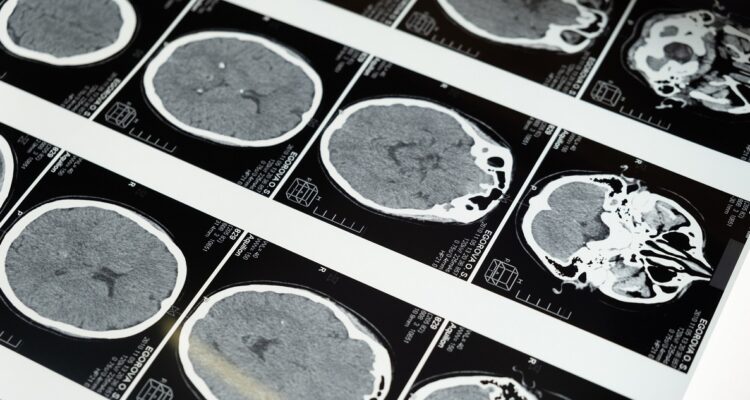

El cerebro humano, y el de otras especies, sigue guardando secretos que son descubiertos conforme avanza la ciencia. Uno de los más recientes es SLYM, una delgada membrana casi indetectable, pero que tendría un rol clave en el funcionamiento del cerebro.

El secreto mejor guardado del cerebro: SLYM, la membrana que podría ayudar a estudiar el Alzheimer